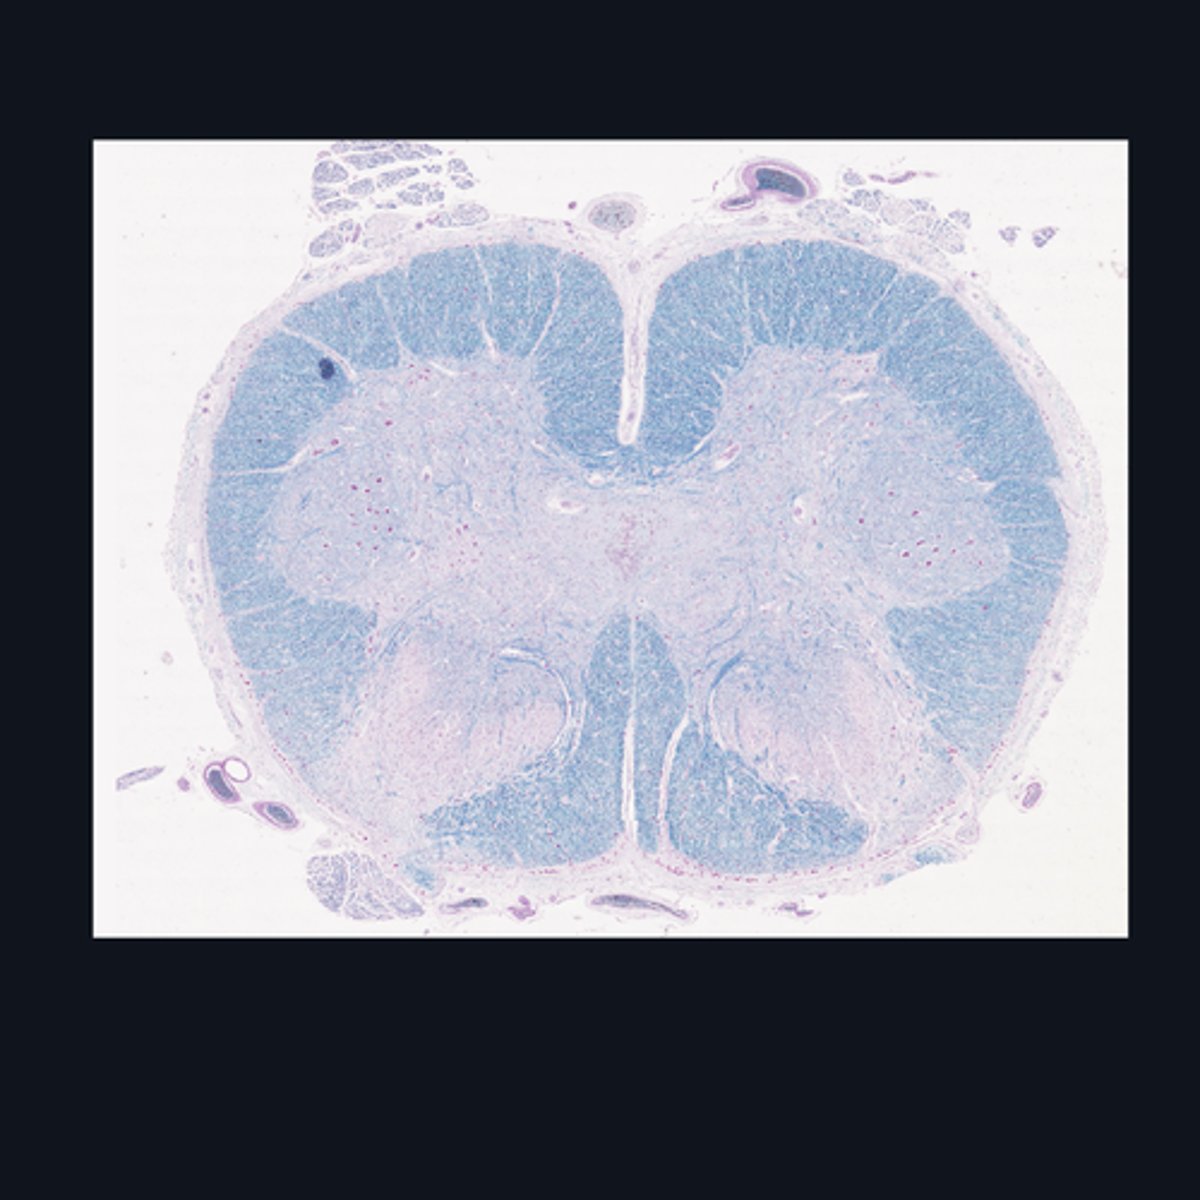

Identify the region of the spinal cord in the given image.

Upper Cervical region

Identify the region of the spinal cord in the given image.

(top to bottom)

White matter

Ventral horn of gray matter

Central canal

Central Commissure

Dorsal horn of the gray matter

Dorsal Midline Sulcus

Identify the structures found in the upper cervical region of the spinal cord.